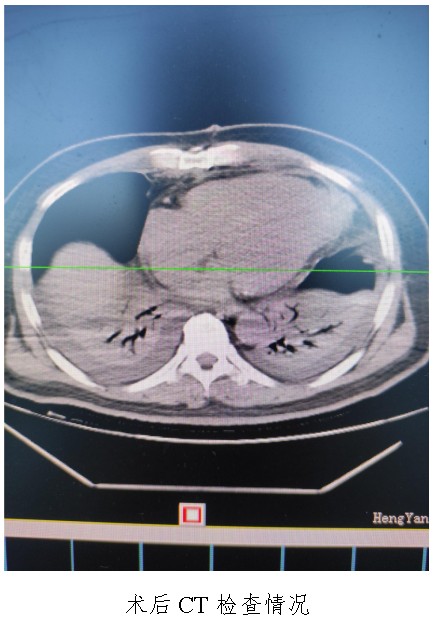

通訊員廖金文報道:一名50歲左心室前壁中下段及心尖部巨大室壁瘤患者在衡陽市中心醫(yī)院心胸外科廖金文主任、屈云劍副主任團(tuán)隊(duì)的精心治療下,接受左心室室壁瘤切除加左心室修補(bǔ)成型手術(shù)后,恢復(fù)良好,于11月1日出院。

10月18日,50歲的孟先生因反復(fù)胸悶氣促一周,夜間不能平臥來衡陽市中心醫(yī)院心胸外科就診,經(jīng)心臟超聲檢查提示左心室前壁中下段及心尖部巨大室壁瘤,66×57mm,最薄處約3mm?;颊哂卸嗄晏悄虿〔∈?,既往有無癥狀心肌梗死病史,曾行PCI治療。入科后,廖金文主任、屈云劍副主任組織心內(nèi)、麻醉、體外循環(huán)、重癥醫(yī)學(xué)科對病人病情進(jìn)行了多學(xué)科討論,一致認(rèn)為手術(shù)是治療該病例的唯一手段。經(jīng)過充分的術(shù)前準(zhǔn)備,10月24日,心臟外科團(tuán)隊(duì)給患者實(shí)施了左心室室壁瘤切除加左心室修補(bǔ)成型手術(shù),手術(shù)順利,術(shù)后經(jīng)過精心的治療管理,患者恢復(fù)良好,康復(fù)出院。該病例的手術(shù)成功,不僅是術(shù)中及手術(shù)團(tuán)隊(duì)智慧的結(jié)晶,也是多學(xué)科合作的結(jié)果,展示了衡陽市中心醫(yī)院處理復(fù)雜危重患者的能力。